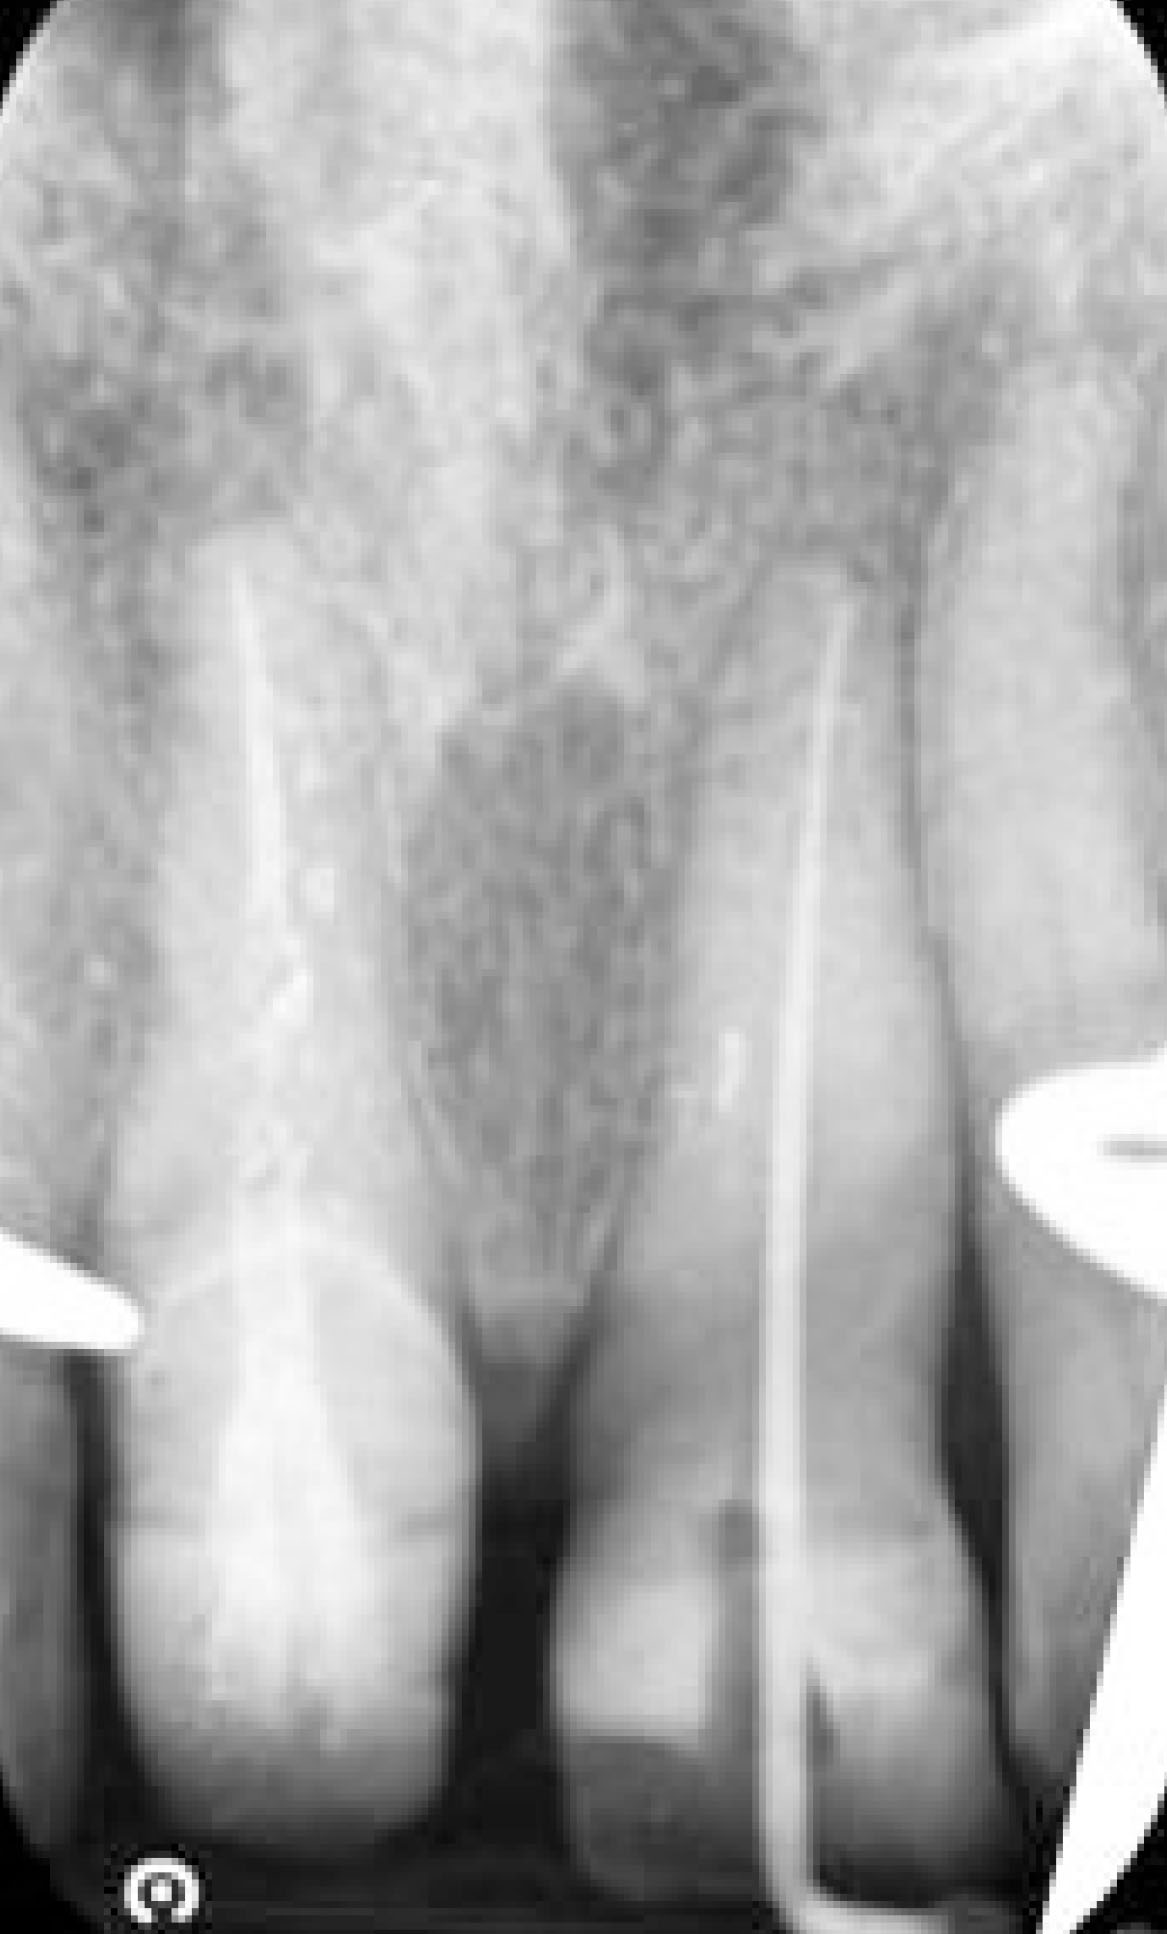

La massima azione microbicida avviene combinando ipoclorito di sodio e laser: una volta inoculato l’ipoclorito all’interno del canale, si porta la fibra (200nm) a circa 1 mm dall’apice (fig. 2), si attiva, quindi, con movimenti circolari in direzione apico-coronale, si percorre il canale in tutta la sua lunghezza. L’operazione, da ripetere tre volte, dura complessivamente 20s e si effettua al termine della fase di strumentazione (fig. 3, 4).

La terapia canalare oggi ha percentuali di successo molto elevate, se vengono seguite meticolosamente le procedure ormai standardizzate di sagomatura, irrigazione e otturazione tridimensionale del canale. È opportuno, però, considerare che, benché l’irrigazione tradizionale (NaOCl 5%+ EDTA 17%) rappresenti ancora il modello di riferimento, numerosi studi hanno evidenziato l’efficacia della disinfezione laser a potenziamento degli irriganti, offrendo strumenti per ridurre ulteriormente gli insuccessi (fig. 8).